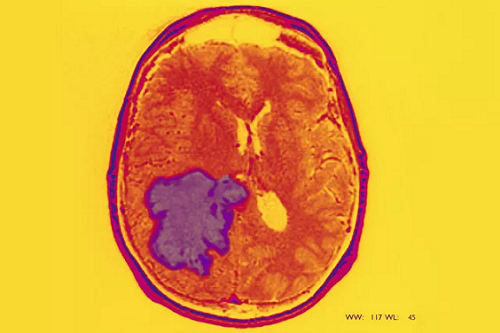

导读:DIPG肿瘤(弥漫性内生性脑桥胶质瘤)作为一种极具挑战性的疾病,近年来在治疗成功案例方面取得了显著进展。这些成功案例不仅反映了医学领域的进步,也为患者和医生提供了宝贵的经验。成立了9年的美国本土海外看病服务机构美联医邦了解到,通过国际合作和技术创新,许多DIPG患者获得了新的生命希望。

首先,海外看病服务机构了解到,一个典型的成功案例是通过多学科联合治疗实现的。这名患者在接受手术、放疗和化疗后,肿瘤得到了有效控制。在治疗过程中,医生们结合了最新的影像技术和分子诊断方法,确保每一步治疗都精准有效。这种多学科综合治疗的方法为其他患者提供了重要的参考。

其次,海外看病机构获悉,某些患者通过参加临床试验获得了显著的治疗效果。例如,一名患有复发性脑DIPG肿瘤的患者,通过参加一项新型免疫疗法的临床试验,肿瘤显著缩小,病情得到了长期控制。这一案例不仅证明了新疗法的有效性,也为其他患者提供了新的治疗选择。

最后,海外看病服务机构美联医邦服务了数千的海外医疗案例,成功案例还包括通过基因组学指导的个性化治疗。一名患者在接受全基因组测序后,医生根据其特定的基因突变制定了个性化的治疗方案,结果显示,肿瘤迅速缩小,患者的生活质量得到了显著改善。这一案例强调了基因组学在个性化治疗中的重要作用。